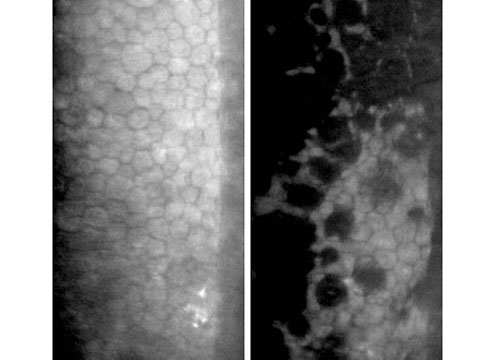

此外,手術前亦建議進行角膜內皮細胞掃瞄,由於角膜內皮是維持角膜清晰的重要組織,內皮細胞亦沒有新增復原能力,如術前發覺出現細胞數量不足或退化情況,進行白內障手術時必須加倍小心,以盡量減少內皮細胞流失,及出現術後持續性角膜水腫的機會。

正常角膜內皮細胞 (左圖) ; 不正常退化內皮細胞(右圖)